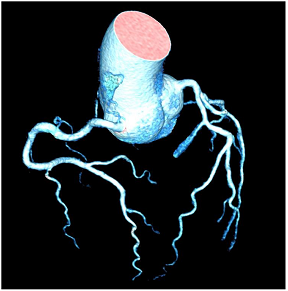

CTCA has the highest negative predictive value of all imaging techniques regarding the exclusion of macrovascular CAD. Often coronary artery tortuosity can be documented (Table 4M). Arterial tortuosity is often associated with arterial hypertension in addition to other factors such as female sex, older age, and other cardiovascular risk factors [73]. In a study population with a high percentage of patients with hypertension (72%), the prevalence of coronary artery tortuosity was 39%; moreover, hypertension was an independent predictor of coronary artery tortuosity in these patients and was associated with increased risk of lacunar infarction [74].

Common non-endocrine causes are aortic coarctation (Table 4N) and renovascular hypertension caused by diseases such as fibromuscular dysplasia (FMD) or renal artery stenosis.

Aortic coarctation is defined as luminal narrowing near the origin of the left subclavian artery and ligamentum arteriosum and is a very rare cause of secondary hypertension with only 0.2% of patients with hypertension affected [82]. Increased afterload due to mechanical obstruction and potential renal ischaemia are regarded as underlying pathomechanisms. CT and, particularly for follow-up, MR angiography are the optimal imaging methods for the detection and quantification of coarctation.

Regarding renovascular hypertension, FMD or renal artery stenosis are the most common causes (Table 4O). Both conditions lead to decreased renal perfusion and subsequent increased systemic blood pressure, but have a different appearance in terms of location: While (atherosclerotic) renal artery stenosis most commonly affects the proximal renal artery, FMD affects the middle segments with alternating strictures and dilatation [83].